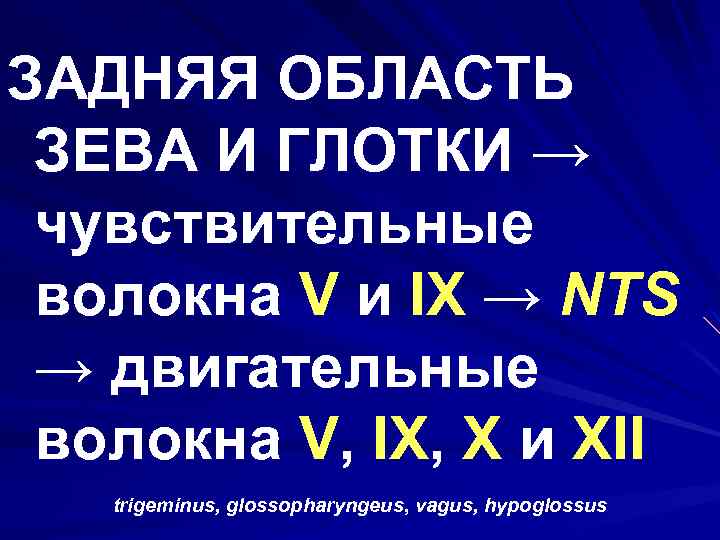

ЗАДНЯЯ ОБЛАСТЬ ЗЕВА И ГЛОТКИ → чувствительные волокна V и IX → NTS → двигательные волокна V, IX, X и XII trigeminus, glossopharyngeus, vagus, hypoglossus

ЗАДНЯЯ ОБЛАСТЬ ЗЕВА И ГЛОТКИ → чувствительные волокна V и IX → NTS → двигательные волокна V, IX, X и XII trigeminus, glossopharyngeus, vagus, hypoglossus